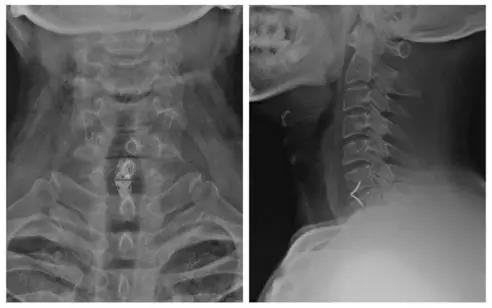

诊断:颈椎病(C6/7)

术后X线正、侧位片